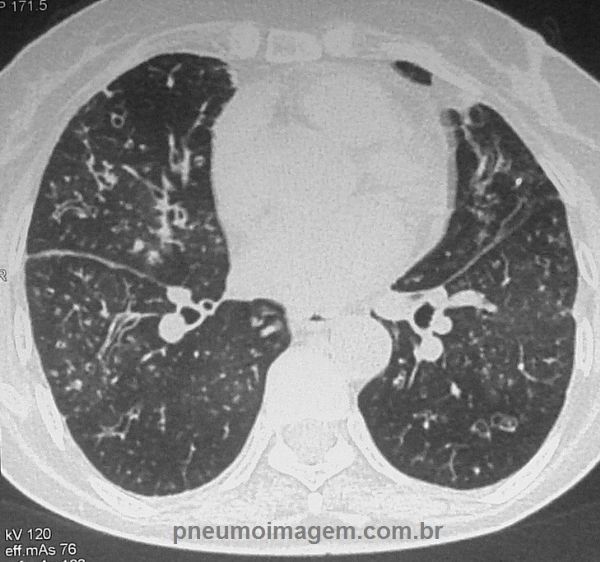

Nesta figura observa-se que as alterações distribuem-se por todo o pulmão.

Este corte ilustra as lesões em lobo médio, língula e lobos inferiores.